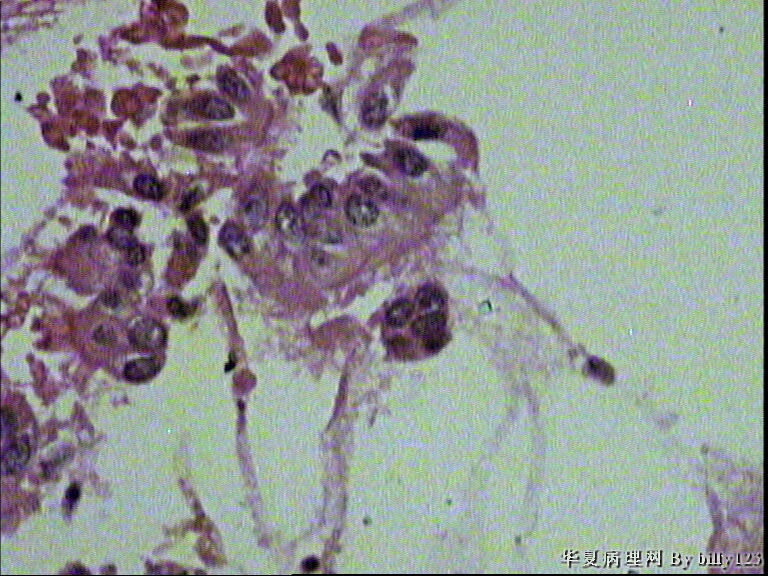

纤支镜活检,女性,75岁,请各位老师指教!

图2